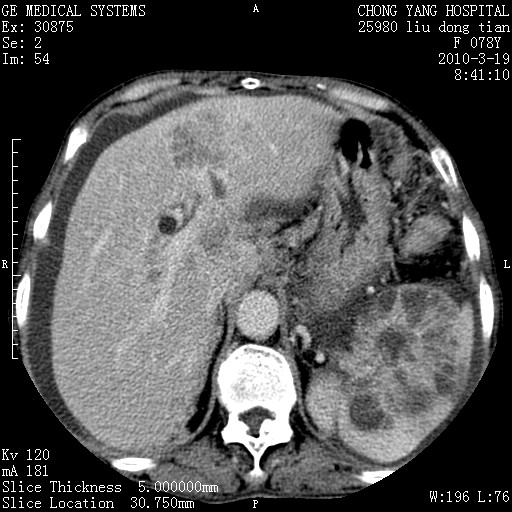

标题: CT25199:F 78Y 腹胀半年 消瘦乏力 [打印本页]

胆囊壁增厚并明显强化,胆囊癌伴多发转移瘤可能性大,淋巴瘤不除外,右肾囊肿,胸腹水.

考虑nhl,肝、脾、腹膜腔及腹膜后多发淋巴结受侵,腹水,右肾囊肿,慢性胆囊炎,右侧少量胸腔积液。

胰头有肿块形成,胰头ca伴肝脾、腹膜腹膜后转移

胆囊有软组织影有强化,支持胆囊癌,肝脾、腹膜后淋巴结转移。

nhl的淋巴结多围绕主动脉,而且主动脉会移位,所以不考虑nhl。

分开来讲:肝左叶、尾叶病灶有不均强化像肝癌;

脾脏病灶无强化,像多发囊肿或淋巴管瘤,不除外淋巴瘤(低强化);

肝门、胰腺头、腹膜后多个团块: 淋巴瘤,转移;

一元论最好了 淋巴瘤所致改变; 胆囊癌转移不像,胆囊周围肝组织清晰,肝癌淋巴结转移?三元论都不止。

胰头ca伴肝脾、腹膜腹膜后转移!

最后报的胰头癌多发转移,脾脏单独考虑囊肿或淋巴管瘤。